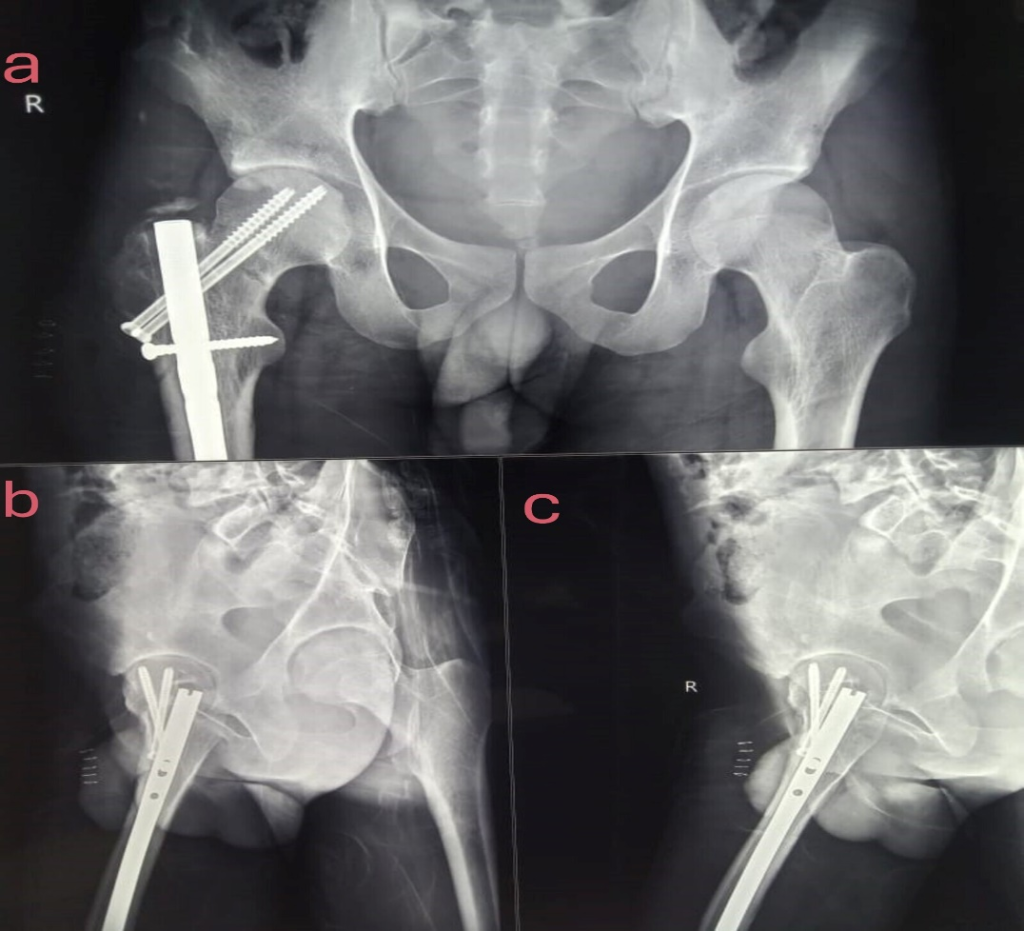

To resolve this issue, we replaced the threaded guide wire with a 2.5 mm Kirschner wire in our case, which allowed us to create a path away from the nail towards the femoral head without breaking upon contact with the nail or proximal locking screw. After reducing the femoral neck fracture, we observed space under the C-arm, with the anterior space visible in the lateral view and the inferior space in the AP view. This space allowed us to insert two K-wires, which were then checked under the C-arm (Fig. 2a-b). Shows two K-wires passed posterior to the nail and missing the nail, with the arrow marked. Afterward, the 2.5 mm Kirschner wire was removed, and the 2.0 mm threaded guide wire was inserted into the path created by the Kirschner wire. Two partially threaded 6.5 mm cannulated compression screws were then inserted, achieving fracture compression and reduction without disturbing the in situ nail, as shown in the post op image in (Fig. 3a-c) it shows post-op image neck of femur fracture in AP (3a, 3b) and lateral images (3c), with well-reduced neck of femur with CCS screw with femur interlocking nail in situ. This approach helped reduce operative time, blood loss, and fracture displacement while minimizing intraoperative and post-operative complications.

Figure 3: Post-op image neck of femur fracture in anteroposterior (a and b) and lateral images (c), with well-reduced neck of femur with cannulated screw screw with femur interlocking nail in situ.